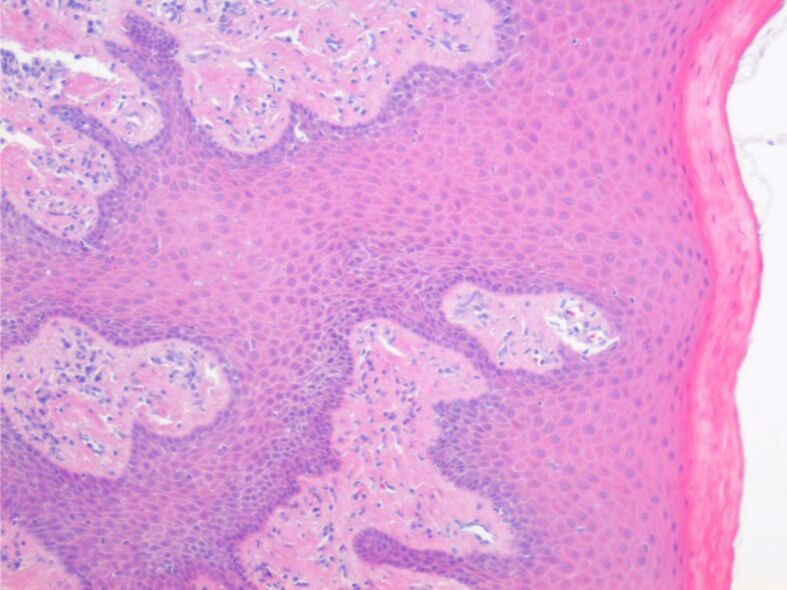

The oral mucosa can suffer a series of traumatic injuries from various causes (bacterial plaque, tartar, fillings, incorrectly adapted prosthesis). A risk factor generating periodontal diseases is represented by fixed orthodontic therapy, if the forces exerted on it are excessive. These forces cause more or less extensive injuries both on the surface and in depth. One of these lesions is gingival hypergrowth. Early injuries concern only the superficial periodontium and are represented by mild or moderate inflammation, gingival hypergrowth, which can be reversible after removing the irritating factor (bacterial plaque, tartar). Advanced injuries are characterized by major clinical, radiological and tissue changes that cause the destruction of the deep periodontium (alveolar bone, deep ligament). Hypergrowth changes may occur at the epithelial level with reduced conjunctival reaction or may predominantly involve fibro-connective structures of the chorion with insignificant reaction in the epithelial component. Through this study, we highlight superficial and deep changes at the gingival and periodontal level.